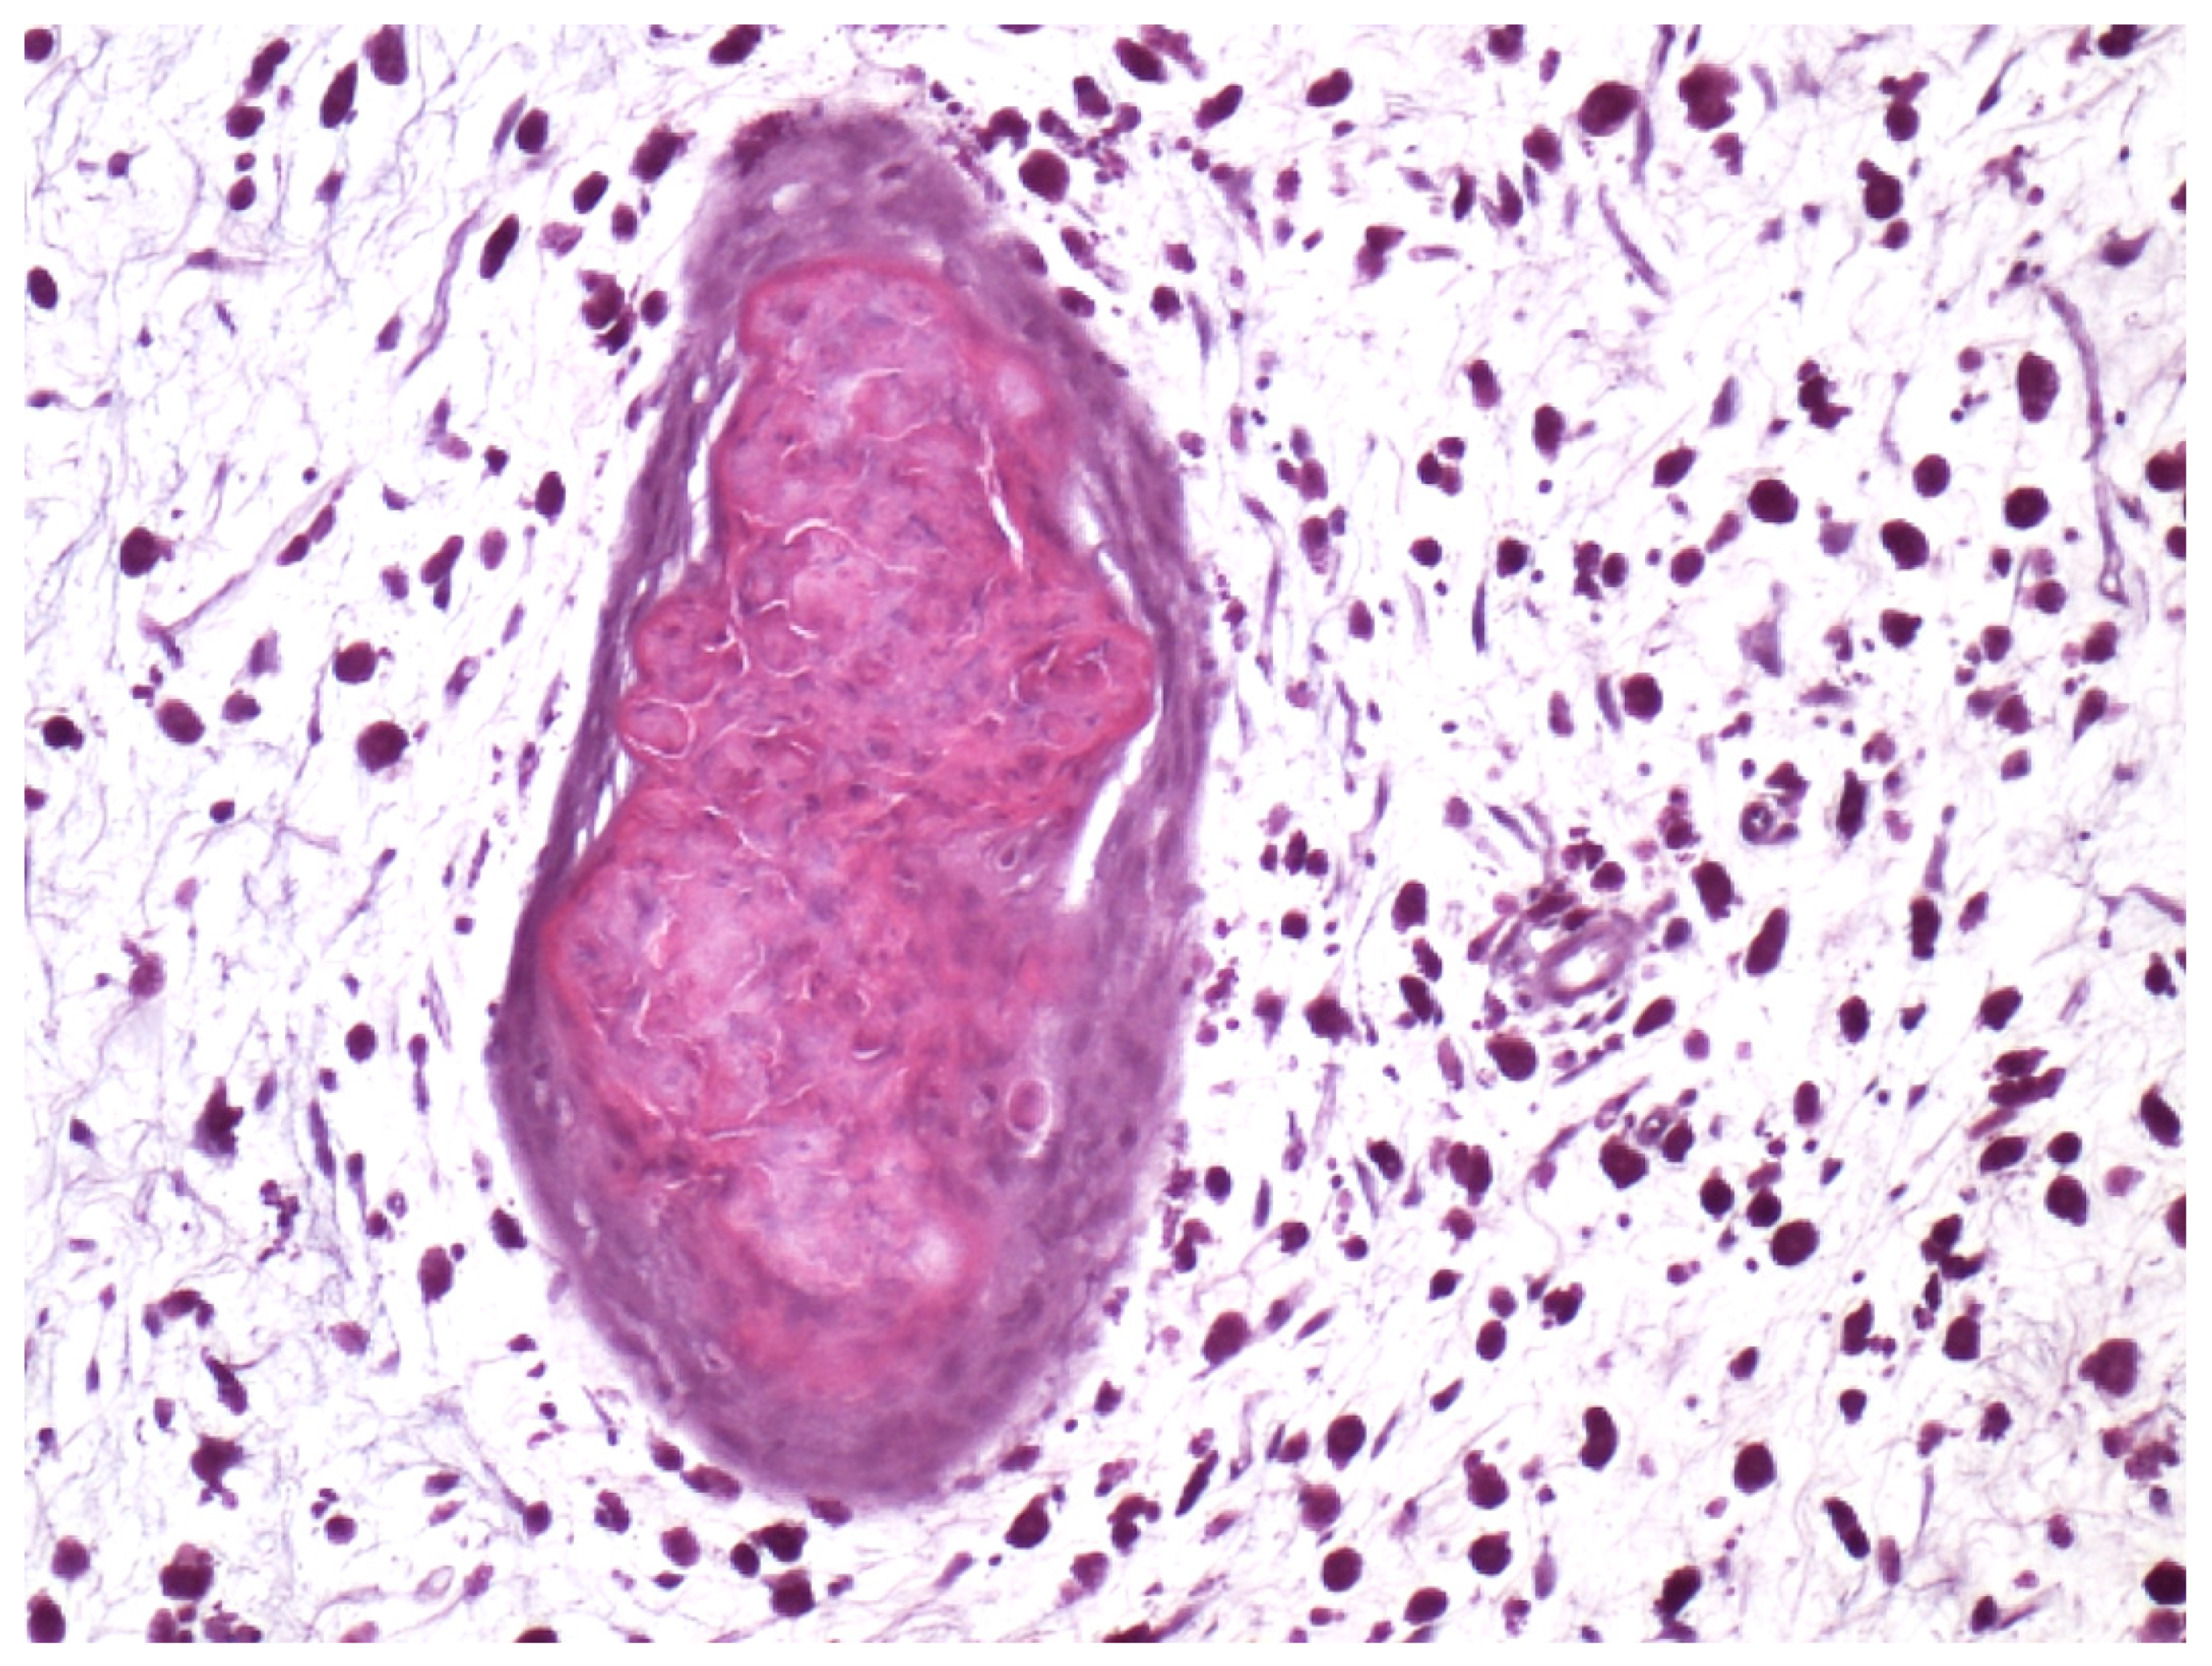

Parasites, granulomas, or both were the most common finding and were most prevalent in the stomach and/or the intestines (Table 1 and Table 2; Figure 2 and Figure 3). Parasitic nematodes were present in the layers of the stomach and attached mesentry of 8 fish (23%), and/or the intestine with attached mesentry in 4/35 fish (11%), and/or the stomach submucosa in 5 fish (14%) (the layer between the lining of the stomach and the muscle layer) (Table 2). Parasites, granulomas, or both were present in control fish and experimental fish from 0 to 38% per group, with no increase with time of out of water (Table 2). In many cases parasites were accompanied by minimal inflammation in the stomach/mesentry and many of the granulomas in the stomach submucosa did not have identifiable parasites (Table 2). There was no damage to the digestive tract, such as perforation of the wall, tissue damage, or infection associated with parasites and inflammation. The number of parasites in sections was small in each fish (up to 5) and inflammation was minimal.

Figure 2. Small granuloma in loose connective tissue with scattered leukocytes. No specific cause was identified.